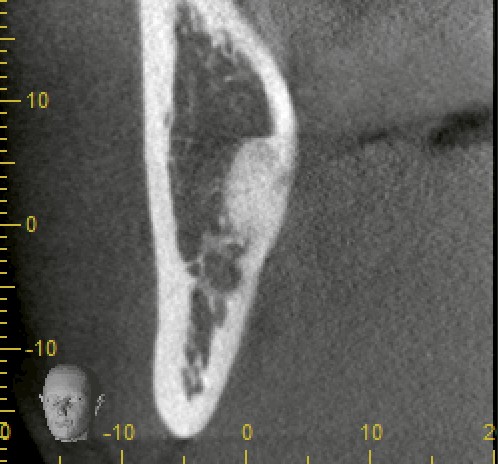

当院にてCT撮影を行ったところ、確かに下歯槽神経に近接していましたが、直接の接触は認められませんでした。

このように、パノラマX線だけでは判断が難しいケースでも、CTによって三次元的に確認することでリスクを正確に分析できます。

根は単根で比較的シンプルな形態であったため、処置は約15分で終了。